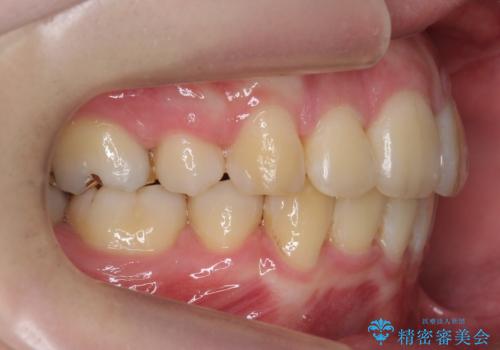

- 前歯のがたつき、前突を主訴に来院。

通常前から4番目の歯を抜歯するのですが、左上5番の形が矮小であったため、そちらを抜歯しました。(患者様の希望にそっています。)

前から5番目の歯を抜くと、長くて1年ほど矯正期間が延長しますが、形に異常がない左上4番を抜かずに保存しています。

治療は長くかかりましたが、正常な形の歯をのこすことができました。